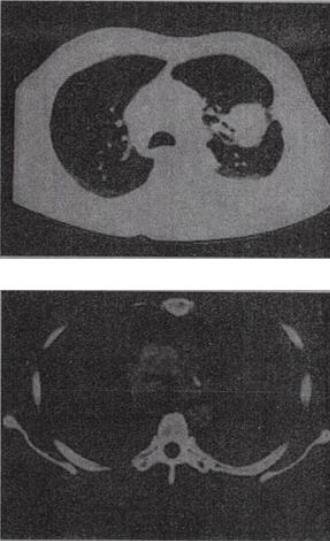

患者,女,68岁,咳嗽伴胸痛闷1个月CT检查如图,最可能的诊断为()。

A、左上肺不张

B、左上肺周围型肺癌伴胸膜转移

C、左上肺血管瘤

D、左上肺软骨肉瘤伴胸膜转移

E、左上肺结核

B